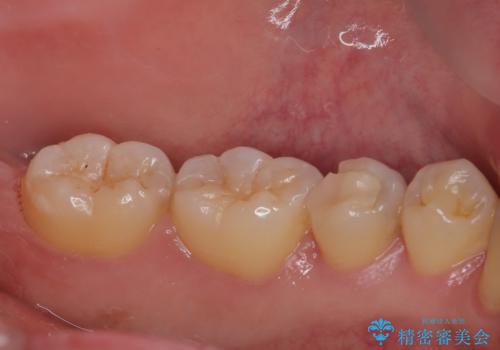

- 左下の奥歯のところがフロスが引っかかったり、ちぎれたりするとのことで来院された患者様です。検査の結果、神経は正常な反応を示し、フロスは引っかかる状態でしたので、虫歯治療も併せて行うためにオールセラミッククラウンによる補綴治療を行っていくことにしました。

拡大鏡視野下でプラスチックの詰め物、虫歯を除去しオールセラミッククラウンに適した形に整えました。

歯と歯茎の間に圧排糸と言われる糸を入れてシリコーン印象材にて型どりをしました。